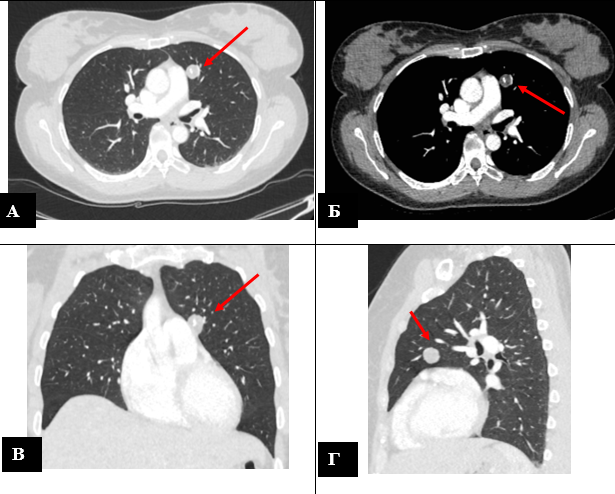

Периферическое новообразование верхней доли левого легкого (гамартома?) – указано стрелкой. Компьютерная томограмма органов грудной клетки в аксиальной проекции: легочный режим (А), средостенный режим (Б); фронтальной проекции (В); сагиттальной проекции (Г).

На снимках врачи заметили небольшое образование в верхней доле левого лёгкого около полутора сантиметров. Никаких жалоб, хорошее самочувствие. И всё же находка требовала внимания: даже небольшие изменения в лёгких нельзя оставлять без оценки специалистов.